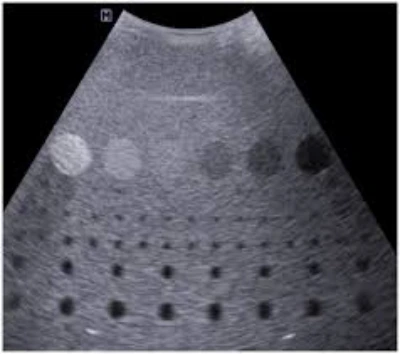

A manutenção de ultrassom hospitalar é um serviço técnico especializado que assegura o funcionamento adequado dos aparelhos utilizados em exames de imagem .

Inclui inspeções, calibração, reparos e substituição de componentes, promovendo precisão e confiabilidade nos resultados.

Com manutenção preventiva, os hospitais evitam falhas, prolongam a vida útil dos equipamentos e mantêm continuidade nos atendimentos.

Esse cuidado técnico contribui para eficiência operacional, qualidade nos diagnósticos e segurança dos pacientes, fortalecendo a confiabilidade dos serviços de imagem e a rotina de procedimentos médicos nas instituições hospitalares.